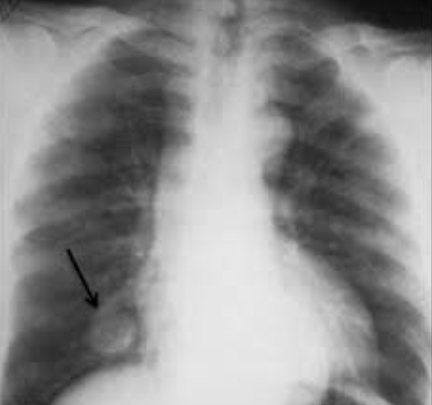

고립성 폐결절 증상

고립성 폐결절의 경우, 많은 사람들이 별다른 증상 없이 우연히 발견되곤 합니다. 그러나 경우에 따라 일부 증상이 나타날 수 있습니다. 이러한 증상은 결절의 크기, 위치, 그리고 원인에 따라 달라질 수 있습니다. 다음은 고립성 폐결절의 일반적인 증상들입니다.

고립성 폐결절은 다양한 원인에 의해 발생할 수 있으며, 이 중 하나는 폐암입니다. 결절의 크기, 모양, 가장자리의 성질, 성장 속도, 그리고 환자의 병력 등에 따라 결절이 암일 가능성을 추정할 수 있습니다.

결절의 크기는 암의 가능성과 큰 연관이 있습니다. 일반적으로 8mm 미만의 결절은 암의 위험이 상대적으로 낮지만, 결절이 커질수록 암일 가능성이 증가합니다. 그러나 크기만으로는 암을 확정할 수 없으며, 다른 속성들도 함께 고려해야 합니다.

예를 들어, 결절의 모양과 가장자리의 성질도 중요한 특징입니다. 부드럽고 둥근 결절은 암의 위험이 더 낮은 편이지만, 모서리가 날카롭거나 불규칙하거나, 속이 공동으로 되어 있는 "스펀지 같은" 결절은 암일 가능성이 더 높습니다.

또한 결절이 시간에 따라 얼마나 빠르게 성장하고 있는지도 중요한 정보입니다. 폐암은 대개 빠르게 성장하므로, 시간이 지남에 따라 결절의 크기가 뚜렷하게 증가하는 것은 암의 신호일 수 있습니다.

따라서 고립성 폐결절이 발견된 경우, 암의 위험성을 정확히 평가하려면 주기적인 흉부 CT 스캔, 결절의 생검 등 다양한 검사가 필요합니다. 이러한 검사 결과를 바탕으로 의사는 최적의 치료 방안을 결정하게 됩니다.